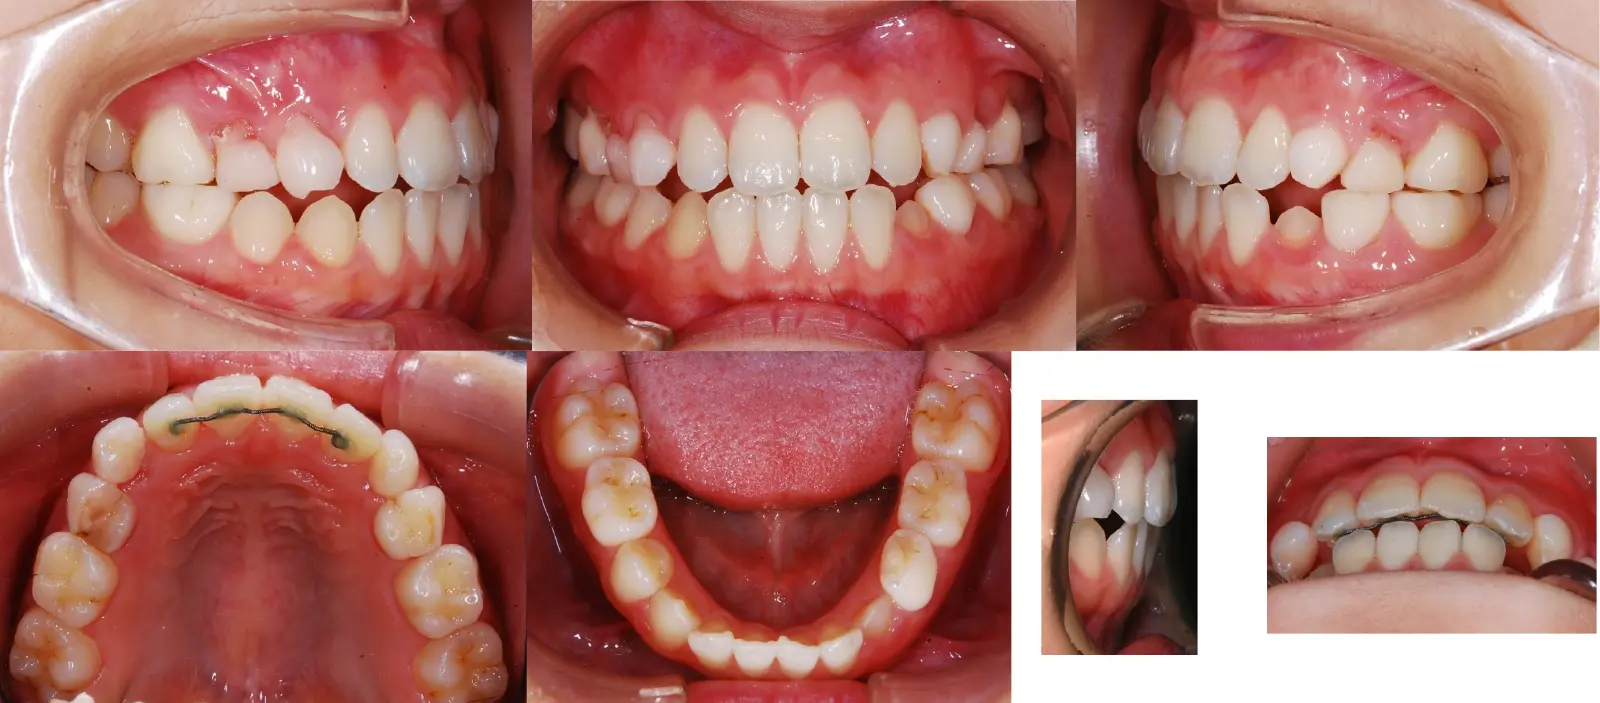

アングルⅡ級 軽度叢生を伴う下顎前突症

第一段階の治療のみで、

永久歯は問題なく萌出し、安定している

- 主訴

歯のガタガタと切端咬合

- 年齢

8歳

- 治療期間

1年3ヶ月

- 治療回数

7回

- 治療に用いた主な装置

2by4、フェイシャルマスク、拡大床

- 治療費

400,000円(税別)トータル料金

- 抜歯部位

非抜歯